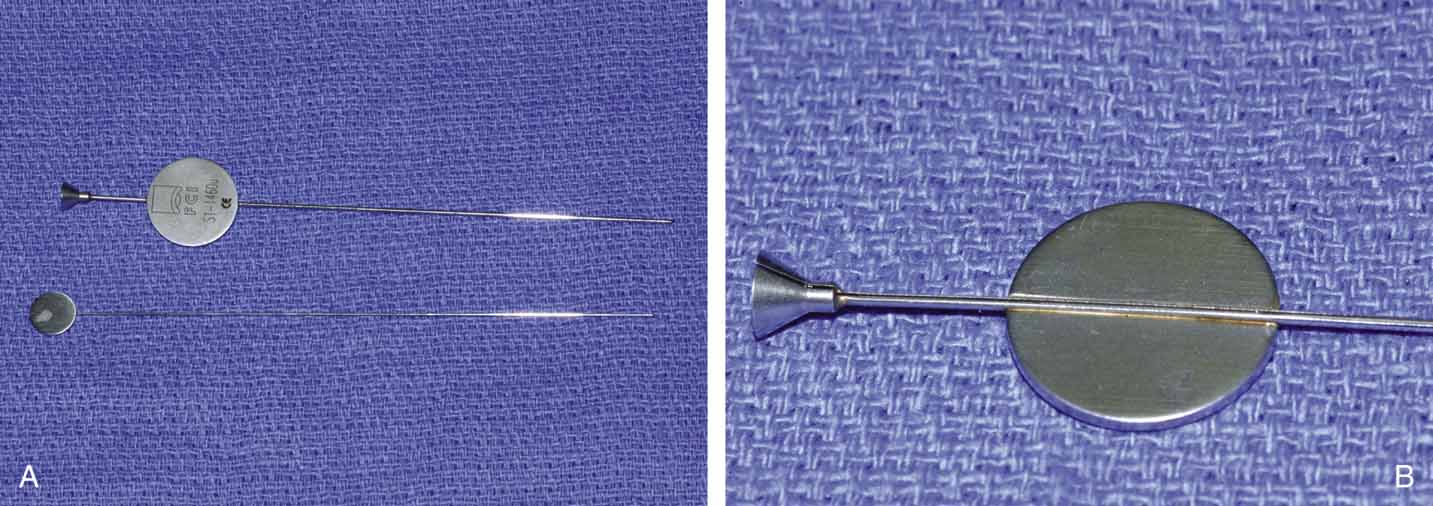

INTUBATION MATERIALS. For many years, bicanalicular Silastic intubation has been the gold standard

for secondary treatment of failed probings.68 Silastic tubing comes packaged in several ways. The important features

to consider in choosing a packaged set for nasolacrimal intubation are

that the metal probe be malleable enough to minimize the trauma to the

nasolacrimal system and that the tubing be bonded sufficiently to the

probes to avoid slipping during passage through the system. Free tubing

can be loaded onto a Quickert probe and passed. Tubing (Silastic, Dow

Corning, New York, NY; tubing 5941, Storz, St. Louis, MO) of 0.025 mm

external diameter is preferred for pediatric and adult

use. The tubing can be glued in place with silicone bonding glue. It is

stretched over a number 0 tapered probe (Quickert 4220, Storz) before

autoclaving. Packaged intubation sets like Crawford Silastic

set (28–0185; hook, 28–0186, Jedmed Instrument Co., St. Louis, MO), O'Donoghue lacrimal tubes (Visitec, Sarsota, FL), and

Guibor lacrimal tubing also are available. They

are more expensive, but avoid the need to prepare the probes with tubing. In 1988, monocanalicular intubation sets became available (Monaka

for a general anesthetic. TECHNIQUES OF INSERTION. Passage and retrieval of the probes may be difficult. It is important to

recognize that intubation of the nasolacrimal system requires the physician

to negotiate several right-angle turns, particularly when

entering through the lower canaliculus. Furthermore, as the probe emerges

near the floor of the nose, it can be difficult to withdraw, especially

in the young child. This problem occurs because the inferior

meatus in a child is flat, and there is little space between the floor

of the nose, the lateral nasal wall, and the inferior turbinate (Fig. 22).73 Silastic intubation of the nasolacrimal duct can be particularly traumatic

if the probes are not malleable (Fig. 23). By the age of 3 years, more space has developed, but it is still